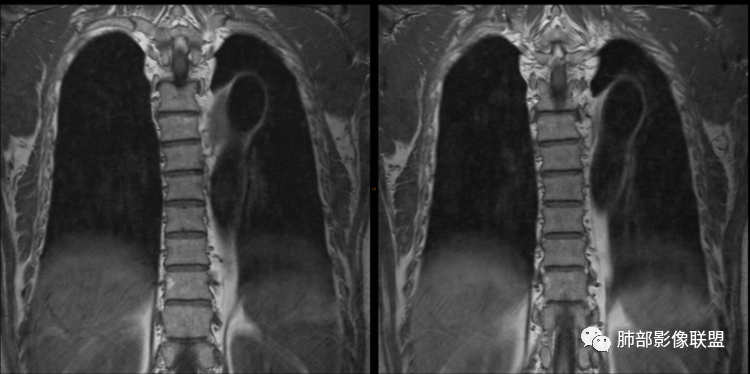

气管、左主支气管后方,食道左侧囊性占位,壁薄且均匀、光滑。气管及左主支气管受压凹陷、变形。

食道也受压变形、移位。

MR所见也差不多。